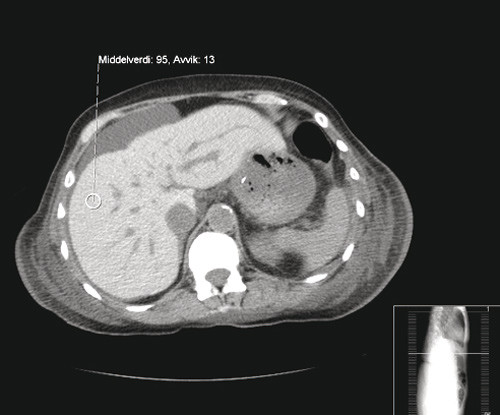

Rettelse En kvinne i 70-årene med redusert allmenntilstand, dyspné og utbredte smerter Kiarash Tazmini, Heidi Nygaard Bakken, Fredrik Hellem Schjesvold Om forfatterne Se alle artikler Kiarash Tazmini Se alle artikler Heidi Nygaard Bakken Se alle artikler Fredrik Hellem Schjesvold () sporsmal_grey_rgb Artikkel Tidsskr Nor Legeforen 2012; 132: 1969 – 72 I Tidsskriftet nr. 17/2012, side 1971 er det feil bilde i figur 3. Her viser vi både figur 2 og riktig figur 3. Figur 2 CT abdomen uten kontrastmiddel fra pasient uten patologiske forandringer Figur 3 CT abdomen uten kontrastmiddel. Bildet viser høy attenuasjon i lever, som ved jernavleiring (dette til sammenlikning med figur 2) Vi beklager feilen, den er rettet i nettutgaven. Kommentarer ( 0 ) Dette kommentarfeltet modereres, men kommentarer blir ikke redaksjonelt behandlet ut over å sikre at de følger retningslinjer for vårt kommentarfelt. Denne artikkelen ble publisert for mer enn 12 måneder siden, og vi har derfor stengt for nye kommentarer. Publisert: 30. oktober 2012 Utgave 20, 30. oktober 2012 Tidsskr Nor Legeforen 30. oktober 2012 doi: 10.4045/tidsskr.12.1152 Opphavsrett: ©️️ Tidsskriftet 2026 PlumX 132 : 2260 Publisert: 30. oktober 2012 Utgave 20, 30. oktober 2012 Tidsskr Nor Legeforen 2012 132 : 2260 doi: 10.4045/tidsskr.12.1152 Opphavsrett: ©️️ Tidsskriftet 2026 Plum Print visual indicator of research metrics PlumX Metrics PDF Får du ikke vist PDF-filen eller vil lagre filen, kan du høyreklikke på PDF-ikonet. Velg «Lagre mål/fil som..» og hent så opp PDF-filen i for eksempel Acrobat Reader. Skriv ut Anbefalte artikler